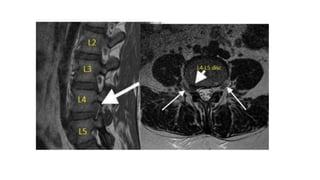

 Chụp cộng hưởng từ (MRI): hình hình ảnh trực tiếp của TVĐĐ

4.1.3.Chẩn đoán định khu

 Bước 1: xác định rễ TK tổn thương (dựa vào chức năng của rễ)

 Bước 2: dựa vào quy luật xung đột đĩa rễ:

- Trường hợp đau một rễ:

* Các rễ bị thương tổn là do đĩa đệm ở tầng trên nó bị thoát vị chèn ép vào, cụ thể:

Thương tổn rễ L2 là do TVĐĐ L1 - L2,

Rễ L3 do TVĐĐ L2 - L3,

Rễ L4 do TVĐĐ L3 - L4

Rễ L5 do TVĐĐ L4 - L5, TVĐĐ L5 - S1

Rễ S1 do TVĐĐ L5 - S1 chèn ép.

4. Chẩn đoánthoát vị đĩa đệm 4.1. Chẩn đoán xác định 4.1.2.Chẩn đoán cận lâm sàng  Chụp cộng hưởng từ (MRI): hình hình ảnh trực tiếp của TVĐĐ  Phương pháp chụp cắt lớp vi tính đĩa đệm: độ nhậy và độ đặc hiệu không cao trong chẩn đoán TVĐĐ.  Phương pháp chụp đĩa đệm (discography): hình ảnh trực tiếp về nhân nhầy của đĩa đệm.  Phương pháp chụp khoang ngoài màng cứng phía trước: hình ảnh gián tiếp đĩa đệm TV  Phương pháp chụp tĩnh mạch gai sống thắt lưng: => gián tiếp thấy hình ảnh đĩa đệm bị thoát vị.

4. Chẩn đoánthoát vị đĩa đệm 4.1. Chẩn đoán xác định 4.1.3.Chẩn đoán định khu  Bước 1: xác định rễ TK tổn thương (dựa vào chức năng của rễ)  Bước 2: dựa vào quy luật xung đột đĩa rễ: - Trường hợp đau một rễ: * Các rễ bị thương tổn là do đĩa đệm ở tầng trên nó bị thoát vị chèn ép vào, cụ thể: Thương tổn rễ L2 là do TVĐĐ L1 - L2, Rễ L3 do TVĐĐ L2 - L3, Rễ L4 do TVĐĐ L3 - L4 Rễ L5 do TVĐĐ L4 - L5, TVĐĐ L5 - S1 Rễ S1 do TVĐĐ L5 - S1 chèn ép. * Thoát vị lỗ ghép: cùng tầng đĩa đệm thoát vị